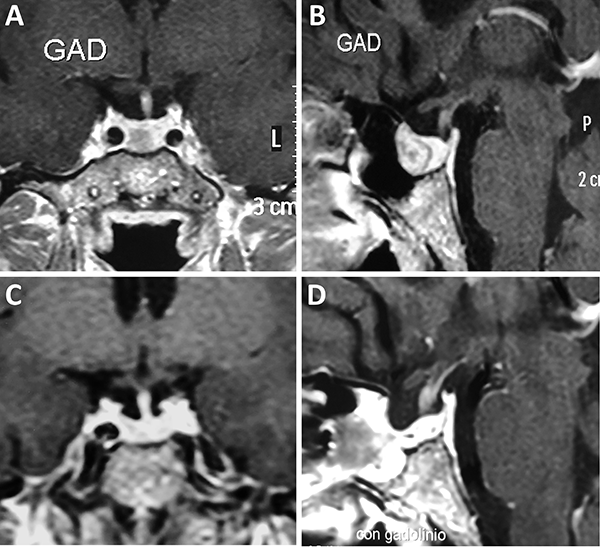

Una clasificación clásica de los adenomas es según su tamaño. Se los clasifica en microadenoma <10 mm (fig. 2), macroadenoma >10 mm (fig. 3), y adenoma gigante > 30 mm (fig. 4). Esta clasificación es importante ya que los índices de remisión están ligados al tamaño del adenoma y también su recidiva.12

Figura 2: Microadenoma. A-B: RM preoperatoria; C-D: RM postoperatoria.

Figura 3: Macroadenoma. A-B: RM preoperatoria; C-D: Campo visual preoperatorio; E-F: RM postoperatoria; G-H: Campo visual postoperatorio.

Figura 4: Adenoma gigante. A-B: RM preoperatoria; C-D: RM postoperatoria.